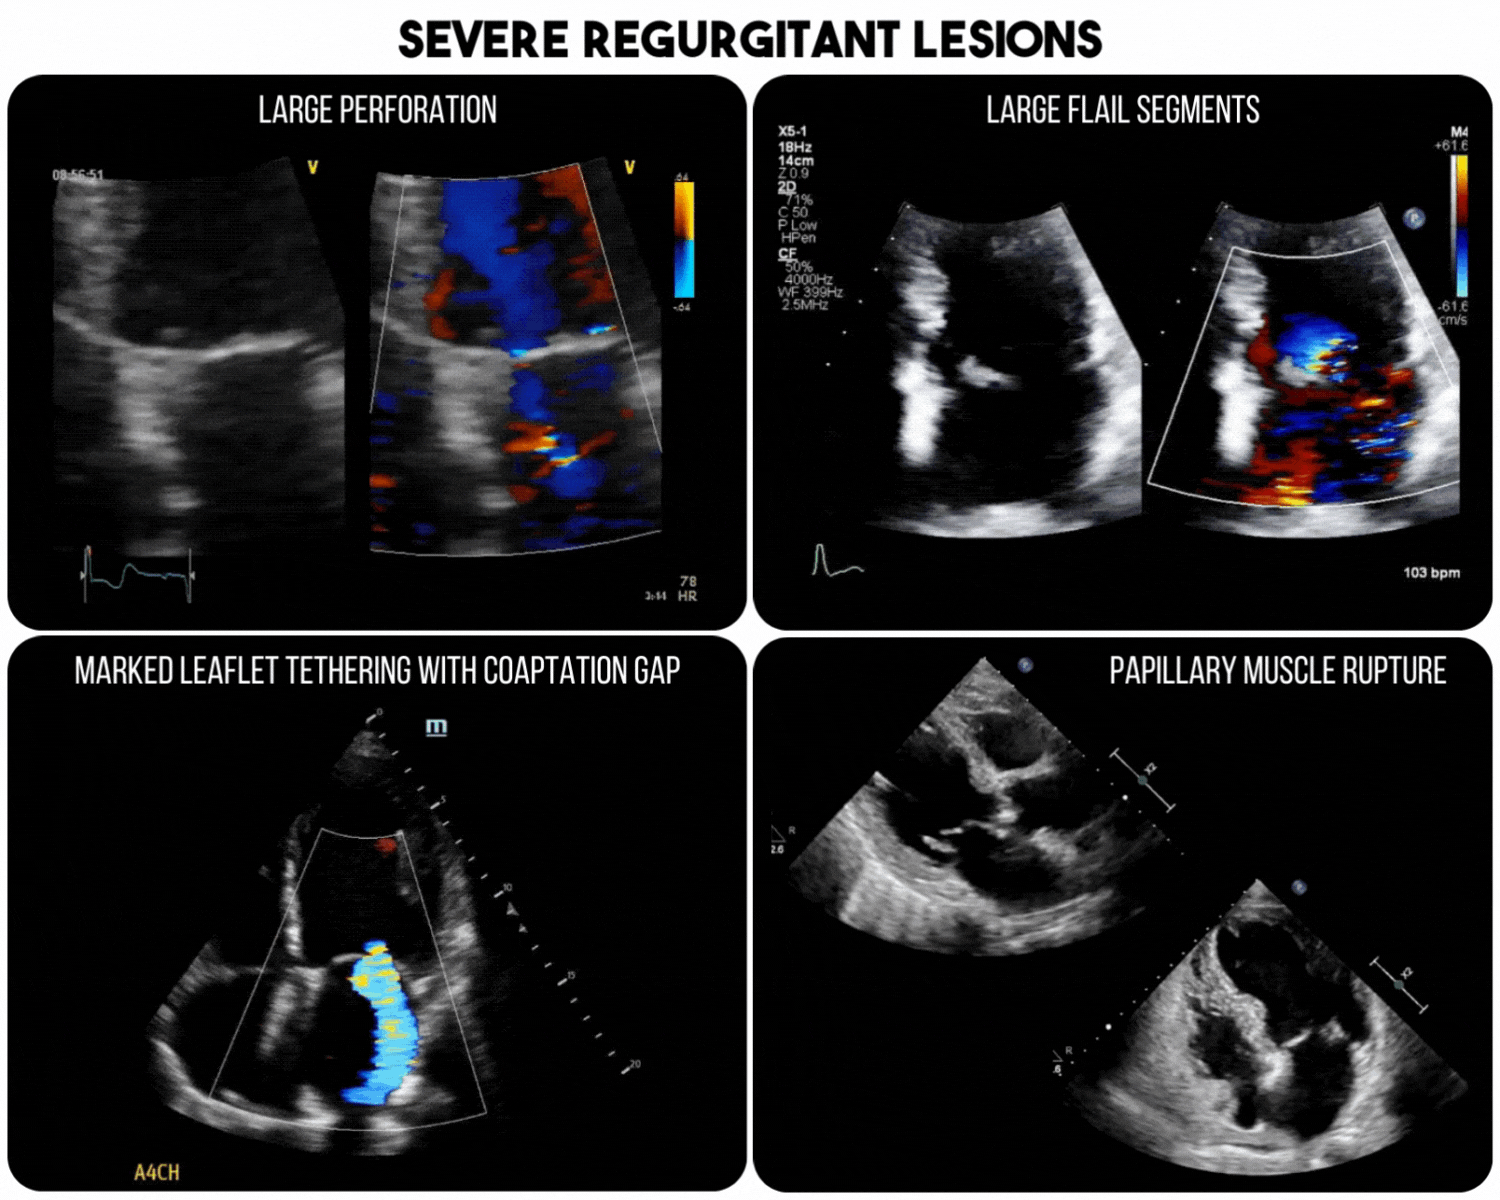

Throughout the 2D exam, close attention for pathology leading to severe regurgitation should be sought, as these have been found to have a high specificity and positive-predictive value for the presence of acute severe MR (Figure 1).3 It is important to note though that absence of these lesions does not rule out severe MR.

Figure 1. Severe regurgitant lesions associated with severe, acute MR